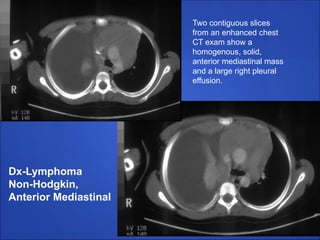

Two contiguous slices

from an enhanced chest

CT exam show a

homogenous, solid,

anterior mediastinal mass

and a large right pleural

effusion.

Dx-Lymphoma

Non-Hodgkin,

Anterior Mediastinal